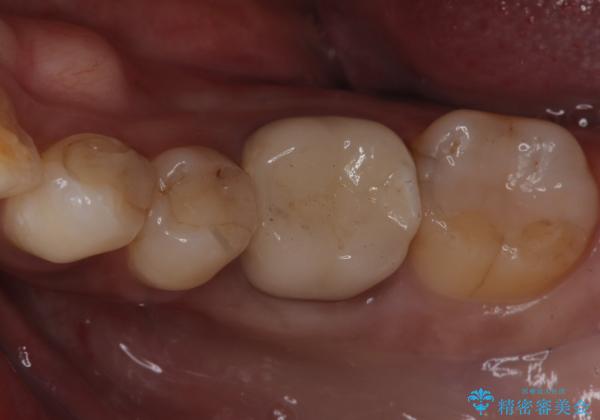

銀歯がとれた セラミックインレーで修復

- 銀歯が取れたとのことで来院されました。

拡大鏡下で丁寧に虫歯を取り除き、セラミックインレーによる修復治療を行いました。

銀歯を固着するセメントは経年劣化し溶け、隙間ができます。そこにプラークが侵入して虫歯が再発します。今回のように銀歯が脱離してしまうこともあります。

今回は銀歯が取れたので、虫歯が神経まで達して痛みが出る前に、強度・審美に優れ、虫歯の再発の少ないセラミックインレーにて治療を行うことができました。